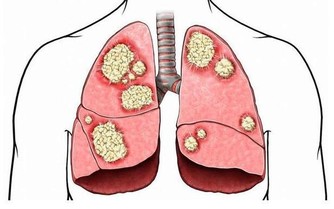

對於這種現象,川嶋朗表示並不樂觀,它聽說過一種說法,人體溫度下降1度,身體免疫機能就可能下降30%,代謝能力也會下降,嚴格來講,就是人體溫度下降,可能會使得患病風險增加。

川嶋朗曾寫過《溫活》相關書籍,在書中它強調的是提升人體溫度,對保養身體有好處,因為在低溫的情況下,血液循環會變差,營養和血液以及氧氣供應就會不及時,免疫系統也會因此受到破壞,身體素質自然也就容易變差,可能會引起相關疾病。